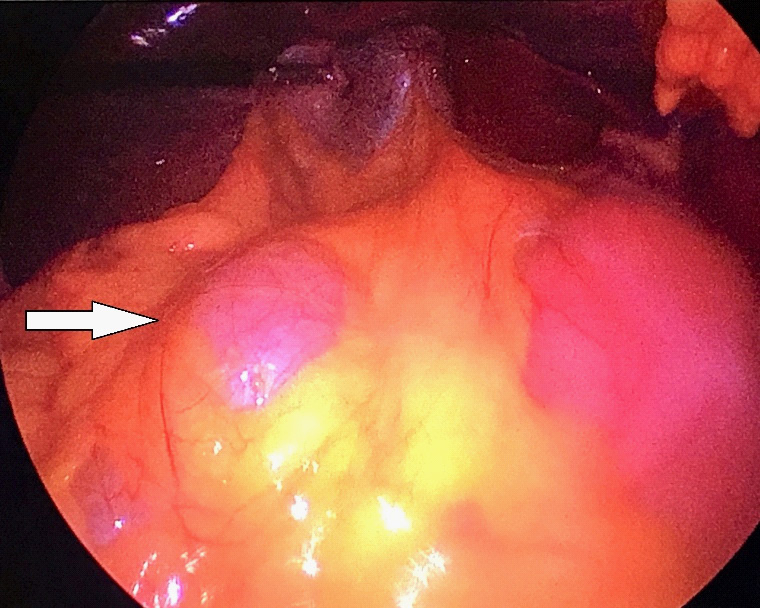

Multidisciplinary team (MDT) meeting recommended to attempt laparoscopic approach; since investigations revealed no biologic or radiologic potentially malignant features. Patient was consented for laparoscopic cholecystectomy and resection of the cystic mass with the possibility of conversion to laparotomy. She was placed in the reverse Trendelenburg with right up tilt position and the procedure was performed using three trocars only (two 5 mm and one 10 mm ports). Initial exploration revealed a large bulge within the mesentery of the right colon (Figure 2). Liver and peritoneal surfaces were examined and noted no abnormality. Adequate exposure was attained using Cattel maneuver (medial visceral rotation of right-sided organs). The uterus and both ovaries looked normal, no attachment with the cyst was identified. Gallbladder was retracted upward and the large cystic lesion was entirely visualized. It appeared to be an oval, thin walled and transparent. It had a regular border with smooth glistening surface containing about 500 ml of serous material. Cyst was easily separable from the adjacent organs. It was totally dissected from the inferior border of the liver and right kidney down to the right iliac fossa. Complete excision of the cyst was done followed by cholecystectomy. The cyst wall components and gallbladder were retrieved through the umbilicus (Figure 3). All her symptoms were disappeared after surgery.

Figure 2:Intraoperative findings.